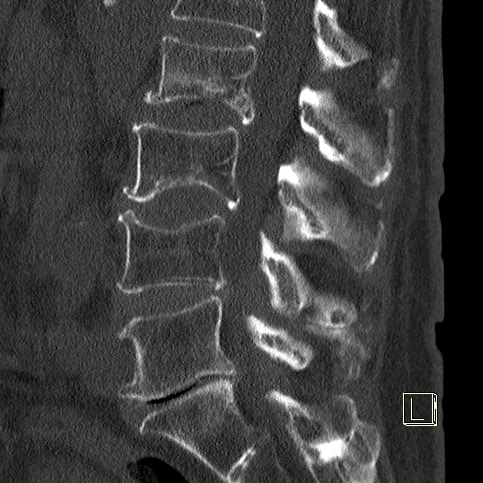

Die Schmerztherapie unter CT-Sicht ist eine prĂ€zise und schonende Methode zur gezielten Behandlung chronischer oder akuter Schmerzen. Durch die computertomographisch gesteuerte Bildgebung kann die Injektion von schmerzlindernden oder entzĂŒndungshemmenden Medikamenten exakt an die betroffene Stelle erfolgen, etwa an die Nervenwurzel oder das Facettengelenk der WirbelsĂ€ule.

Die Behandlung erfolgt in bequemer Liegeposition und dauert meist nur wenige Minuten. Nach einer örtlichen BetĂ€ubung wird eine feine Nadel unter CT-Kontrolle millimetergenau platziert. Anschließend wird das Medikament verabreicht, um Schmerzen gezielt zu lindern und EntzĂŒndungen zu reduzieren.

Ziel der Therapie ist die Schmerzleitung zu unterbrechen. Direkte Kortisongaben fĂŒhren an den Bandscheiben zu einem entwĂ€ssernden und damit abschwellenden Effekt mit nachfolgender Verringerung der mechanischen Nervenwurzelreizung durch Bandscheibenvorwölbung oder -vorfall.

• Vorbefunde: Um die Injektion prĂ€zise setzen zu können, benötigen wir unbedingt relevante medizinische Vorbefunde sowie aktuelle MRT- oder CT-Bilder. Ohne diese Unterlagen ist eine sichere und zielgerichtete Behandlung nicht möglich.